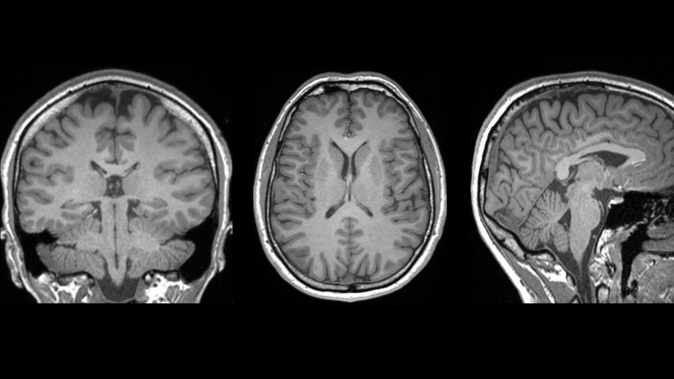

Their newly published study, led by Auckland University of Technology (AUT) researcher Christi Essex, used an advanced MRI technique to scan the brains of young males who had recently suffered head injuries.

Initially, a third of participants suffering from mTBIs showed these markers – but that rate rose to more than 80% when the team used a more sensitive analysis method.